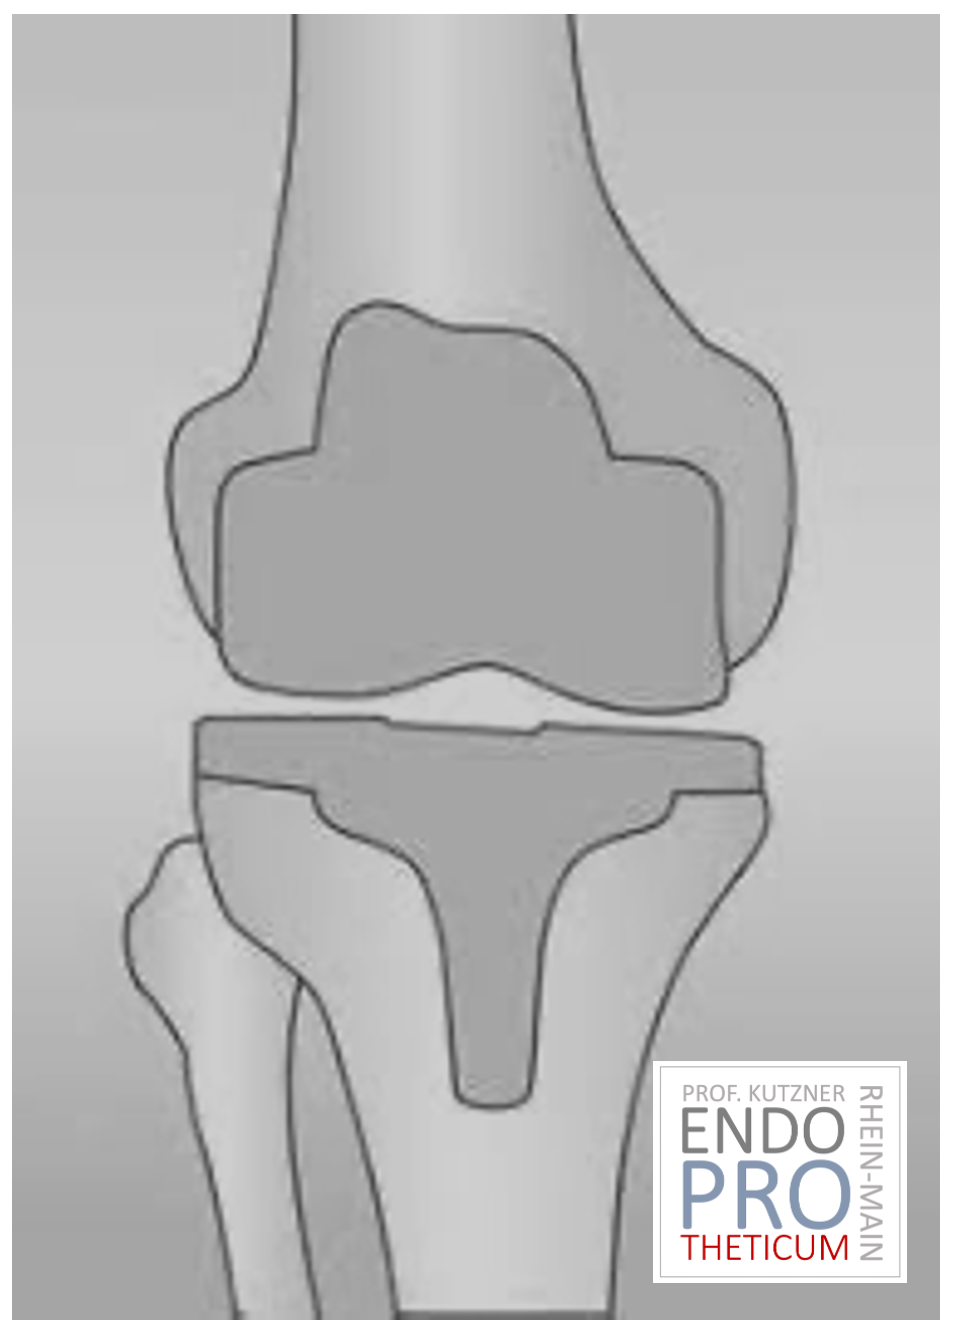

ATR (ARTICULACIÓN ARTIFICIAL DE LA RODILLA)

La articulación de rodilla artificial reemplaza la superficie del cartílago destruida por la osteoartritis. El hueso subyacente del fémur y la cabeza tibial permanece intacto. Algunos comparan una articulación artificial moderna de rodilla con la coronación de un diente; el término exacto es el llamado rejuvenecimiento bicondilar. Entre las nuevas superficies de la parte superior e inferior de la pierna se encuentra la llamada incrustación de un plástico blanco especialmente endurecido, que en la imagen de rayos X se puede ver como la distancia entre las piezas metálicas.